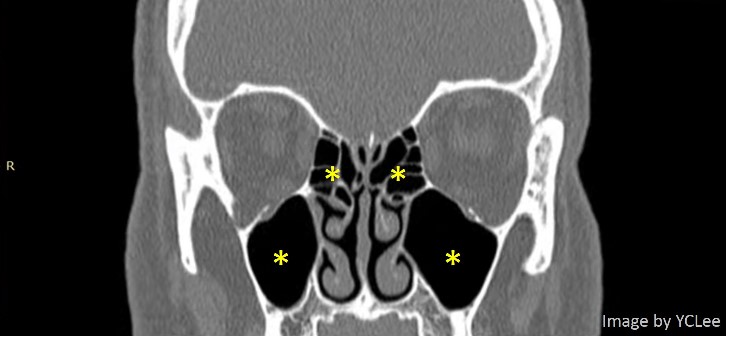

下圖是頭部電腦斷層影像,黃色星號位置即是鼻竇位置。